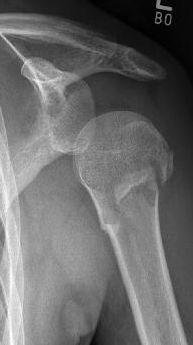

Picture: Here is a subcapital upper arm break in a young woman. An angle stable plate osteosynthesis was performed to stabilize the head in correct position to the humeral shaft and shoulder joint. Especially in young patients, We strive to treat non-invasively and as gently as possible. This possibility is often due to the bone quality in young as opposed to older people.